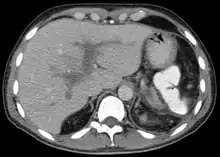

Portal vein thrombosis seen with computed tomography.

Portal vein thrombosis (PVT) is a vascular disease of the liver that occurs when a blood clot occurs in the hepatic portal vein, which can lead to increased pressure in the portal vein system and reduced blood supply to the liver. The mortality rate is approximately 1 in 10.[1]